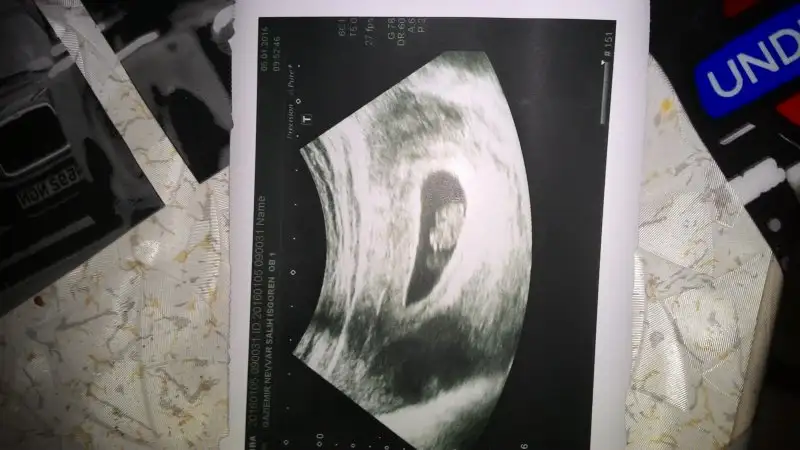

Normalde kiza benziyor canim. Ama kesen benimkiyle ayni herkes bana kiz demisti dr. Erkek dedi. Hakkinda hayirlisi canim gonlundeki hakkinda hayirli olsin ins.Banada yorum yparmisin cnm bide senin yorumunu almak istedim8 haftalik

Banada yorum yaparmısın ikiside karından biri 8 diğeri 13 haftalıkCnm daha çok erken en az 6 haftalık olsun tekrar yolla.

Banada yorum yaparmısın ikiside karından biri 8 diğeri 13 haftalık

Erkege benziyor canim.E Elif sevval yorum yaparmısın